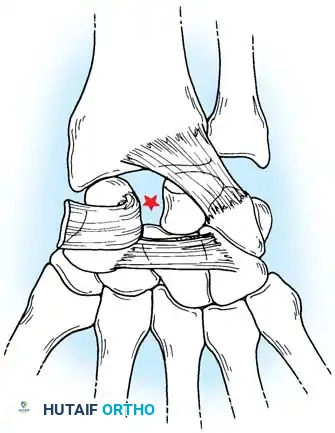

Closed reduction with percutaneous pinning (placing 0.045-inch K-wires from the scaphoid to the capitate and lunate) can be attempted. However, open reduction through a dorsal approach is generally preferred. This allows direct closure of the scapholunate gap, K-wire fixation, and primary repair of the dorsal SL interosseous ligament using suture anchors.

Surgical Management of Scapholunate Dissociation

Acute Injuries (<4 weeks):